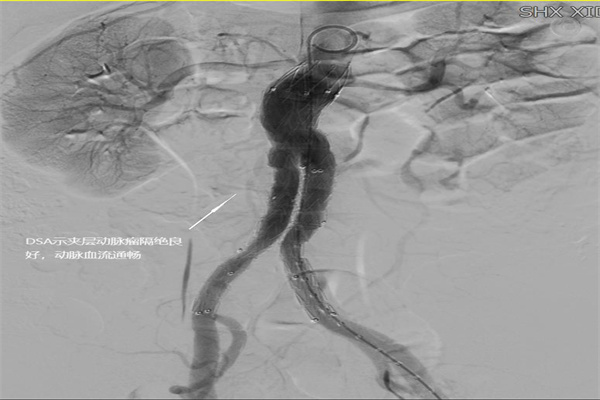

圖1:術(shù)前DSA造影圖

在完善各項(xiàng)術(shù)前檢查后,神經(jīng)內(nèi)科介入團(tuán)隊(duì)在西安交通大學(xué)第一附屬醫(yī)院血管外科蔡惠副主任醫(yī)師的指導(dǎo)下,為張叔成功施行了經(jīng)股動(dòng)脈置管植入覆膜支架。手術(shù)將3處動(dòng)脈瘤腔隔絕,歷時(shí)1個(gè)小時(shí)順利完成。